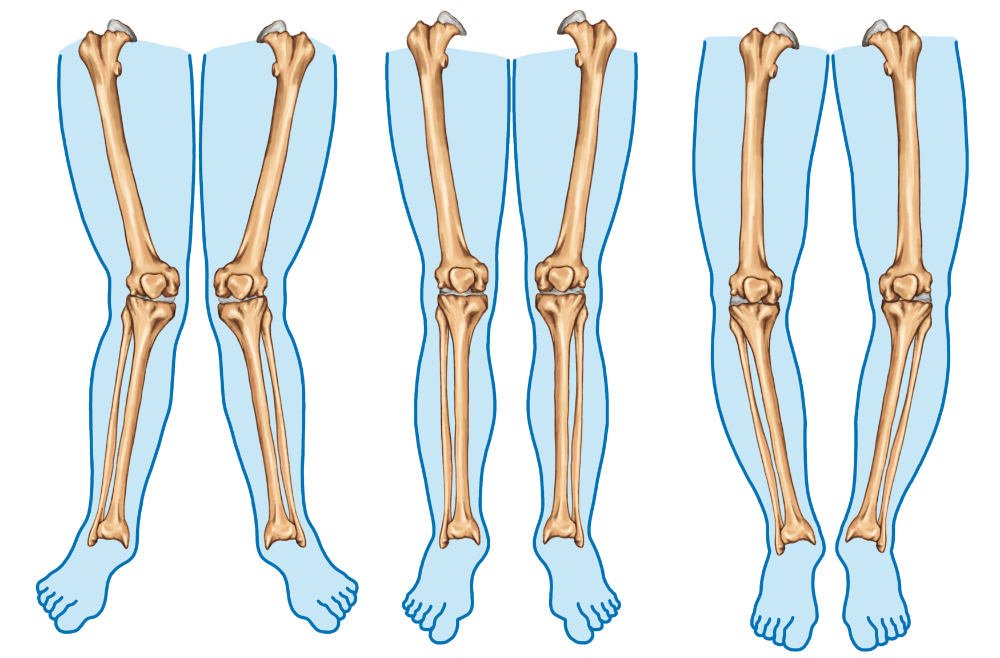

| Valgus | The bone beyond the joint which qualifies the term is directed away from the midline of the body.eg. Coxa valgus Cubitus valgus Genu valgus | ![]() |

| Varus | The bone beyond the joint which qualifies the term is directed towards the midline of the body.e.g. Coxa varus- Cubitus varus- Genu varus | ![]() |